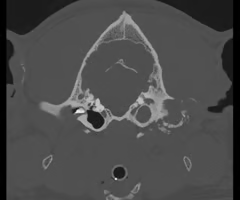

What modality of imaging is more commonly used to view the tympanic bulla?

CT